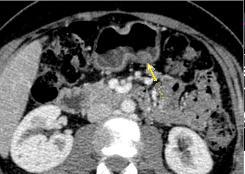

Image TDM hyperdense en nodulaire

endoluminale gastrique ( hypervascularite ) du

carcinoma de endocrine a petit courbure de l'

estomac |